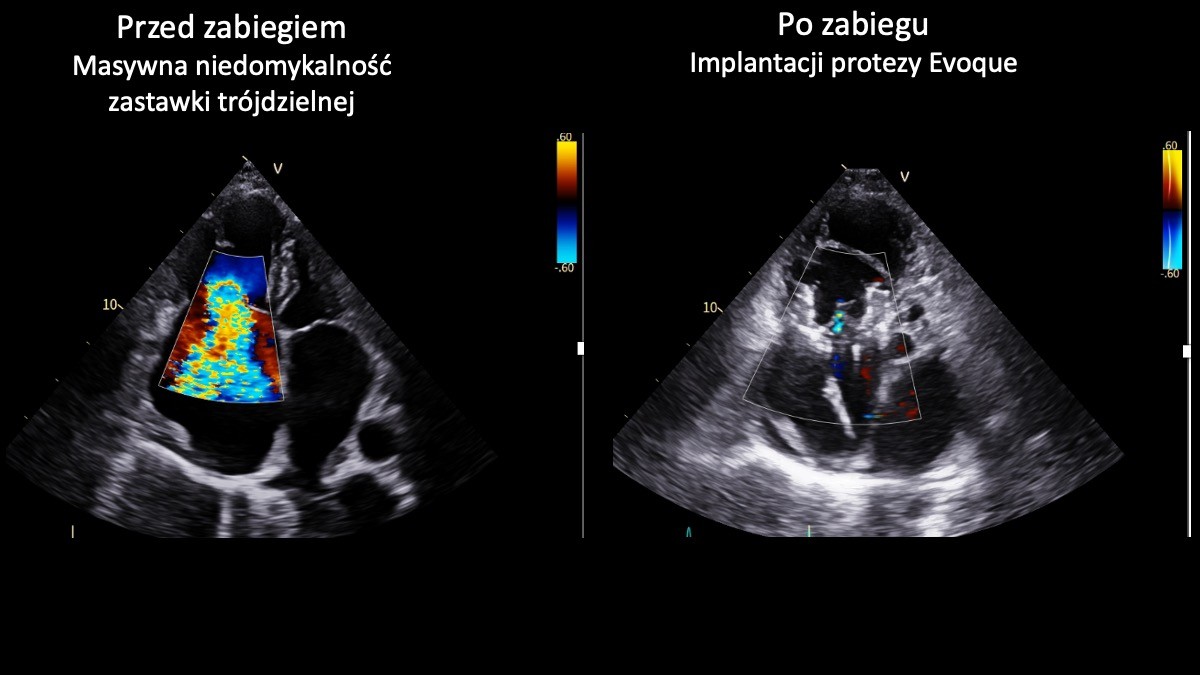

W UCK w Gdańsku przeprowadzili nowatorskie zabiegi serca z wykorzystaniem technologii 3D